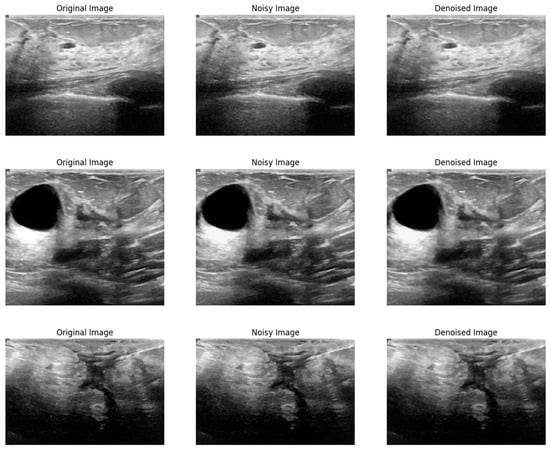

Figure 2 illustrates the visual effectiveness of the proposed denoising method. The figure displays three images for comparison: the original noise-free image, the image corrupted by Gaussian noise, and the image after being denoised using the proposed method. This visual comparison provides a qualitative assessment of the denoising performance, supplementing the quantitative results discussed earlier. The original image serves as a reference, showing the image without any noise interference. The noisy image, corrupted by Gaussian noise, exhibits significant visual distortions that obscure finer details and compromise the visibility of important structural information. In contrast, the denoised image produced by the proposed method shows a remarkable reduction in noise levels, with enhanced clarity and preservation of structural details. This comparison clearly demonstrates the ability of the proposed method to effectively remove noise while maintaining the quality and integrity of the original image.

Figure 2.

Visual comparison of the proposed method on Gaussian noise.